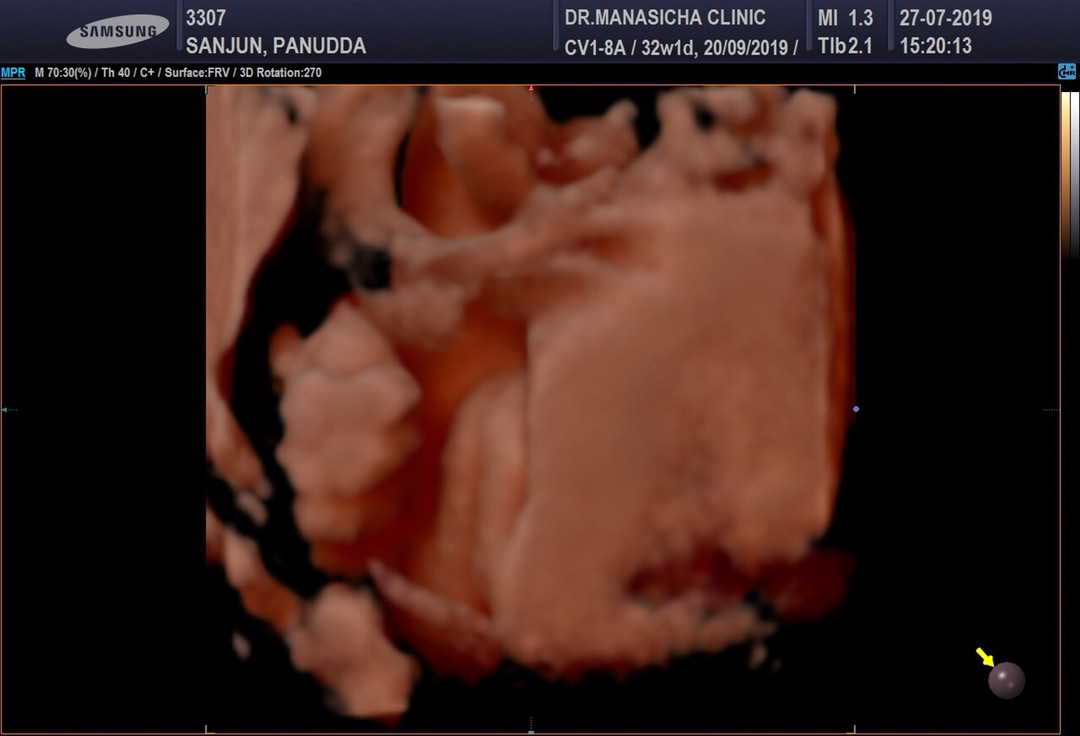

ปู้จายคร๊าบบ😆😆

มีจู๋ค้าบบ 🤣❤️